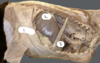

6

Q

A

6 Caudal groove

7 Dorsal ruminal sac

8 Atrium

9 Ventral ruminal sac

11 Right Dorsal coronary groove

12 Right Ventral coronary groove

13 Caudodorsal blind sac

14 Caudoventral blind sac

17 Right accessory groove

18 Insula ruminis (ruminal island)